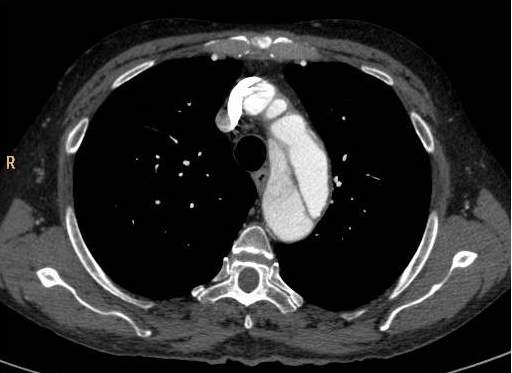

Fig.1., 2.: Hypertrophic obstructive cardiomyopathy: Longitudinal and short axis slices of delayed enhancement of contrast material in the heart: pathologic enhancement is visible in the myocardium in the asymmetrically thickened left ventricular wall, referring to a degenerative-fibrotic process.